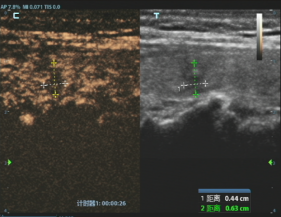

消融前病灶

经过严谨评估,刘女士首先接受了甲状腺穿刺活检。病理结果证实了最坏的猜想——甲状腺乳头状癌。但紧随其后的详细评估,却带来了好消息,结节微小、单发、未转移、未侵犯包膜,完全符合射频消融治疗的黄金指征。

这意味着,不用传统开刀手术,仅通过一根细针,在超声的实时引导下,就可以用热量精准“消灭”这个病灶。主管医师杨波波向刘女士详细解释,“它能最大程度保留你的甲状腺功能,脖子上不会留疤,恢复也快,更无需因此终身服药。”